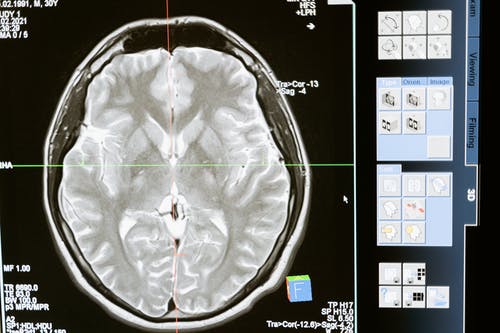

During each stage, the team studied the behavior of the mice to monitor the effects of the disease on the brain (specifically the hippocampus) and conducted “a molecular analysis to measure gene expression and protein levels,” according to their paper, published in Genome Medicine. This allowed them to determine how an unhealthy brain looks compared to a healthy one. They reported, “Our comparison between AD progression and healthy aging revealed certain commonalities, such as the upregulation of microglial and inflammation markers.”